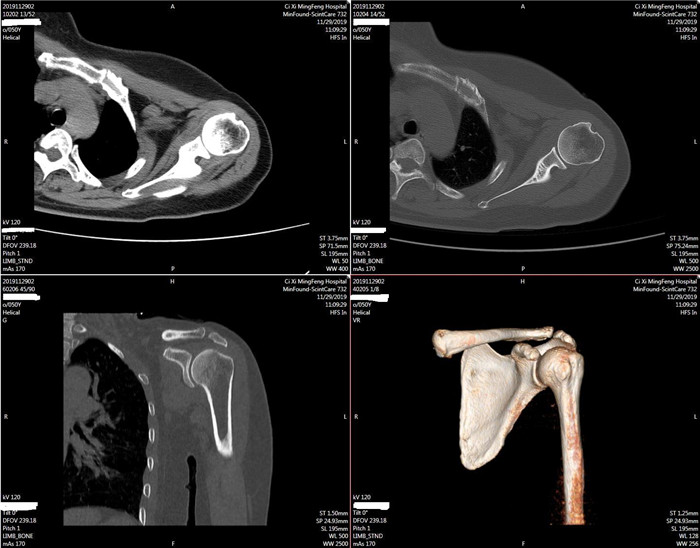

明峰CT搭載了領(lǐng)先的硬件技術(shù)平臺及系統(tǒng),強大的掃描能力可滿足臨床的各種要求,呈現(xiàn)更極致的細節(jié),為各臨床科室提供高品質(zhì)的圖像。薄層掃描,消除部分容積效應,提高各向同性。配合高分辨率算法,有助于細微結(jié)構(gòu)和形態(tài)學顯示。